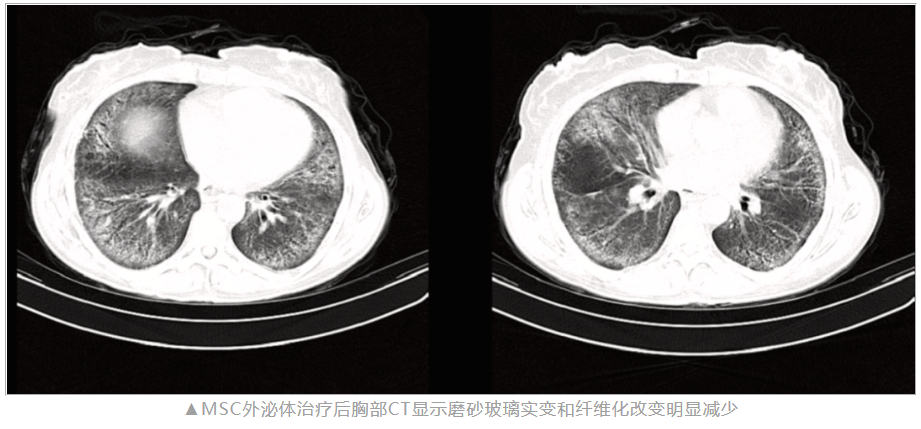

过程:患者接受了共计八次的 MSC-EVs 静脉输注。应用四周后,患者反馈自身呼吸困难、咳嗽等症状得到显著缓解。通过胸部CT扫描结果可见,肺部的玻璃样密度以及纤维化病变均有明显减轻。

影像学检查结果:治疗后两个月的胸部CT扫描显示玻璃样密度和纤维化改变显著减少。